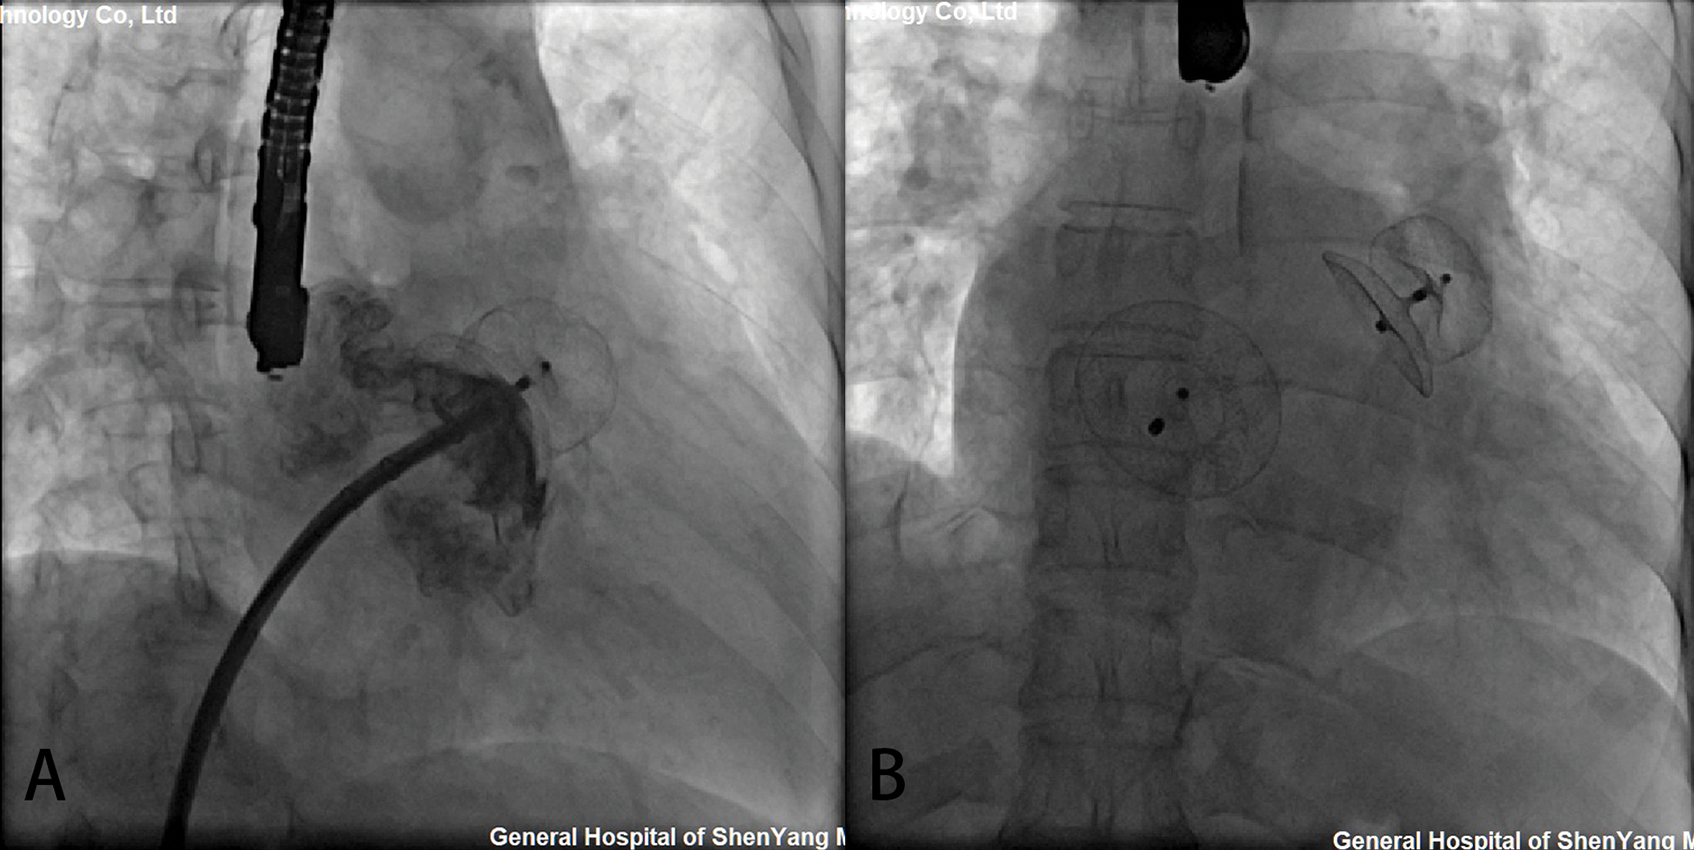

Simultaneous LAA and congenital defect devices were successfully implanted in all the patients (Table 2). The compression rate of the LAA occluder was 4.5%–19.3%. LAAC using 7 ACP2 left atrial appendage occluders and 20 LACBES occluders were successfully performed through the interatrial communication, followed by simultaneously transcatheter interatrial communication closure (Fig. 2). LAAC was successfully performed in 25 patients after only one attempt except for two attempts in two cases using LACBES occluders; after release in the landing area, the LAA occluder was slightly pulled and displaced. The occluder was successfully retreated. After changing the proper size of the LAA occluder, the occluder was stable without displacement. No complications, such as pericardial bleeding, were found after the repeat operation. In one case, a 46 mm domestic ASD occluder with a 1 cm hole was manually implanted after PLAAC as high mean pulmonary artery pressure. Another 26 ASD/PFO patients experienced successful closure of interatrial communication after PLAAC. There was no significant difference in fluoroscopy time between the ACP2 or LACBES occluders groups (15.2 ± 0.1 vs. 15.0 ± 1.2 min, P = 0.749). Of the 23 patients who underwent coronary angiography, 20 patients had normal results except for coronary artery disease in 3 patients, and no further intervention was required.

Figure 2: Simultaneous transcatheter LAA and CHD closures. (A) The delivery sheaths were successfully transported to the LAA via atrial septal communication. After LAAC, the position and residual shunting of the LAA occluder was evaluated by contrast medium and TEE; (B) The shape and position of the occluders were observed by fluoroscopy after simultaneous LAAC and ASD occlusion

The perioperative successful rate of simultaneous PLAAC and congenital defect closure device was 96.3%. One patient developed cardiac tamponade 30 hours after closure. A large amount of pericardial effusion was found by TTE. Pericardiocentesis was performed to drain the effusion. On a postoperative day 5, open-heart surgery was performed for ongoing bleeding. Both LAA and ASD occluders were removed, and ASD was repaired. The ruptured left atrium and the left upper pulmonary vein were repaired. This patient was discharged on the ninth day after surgery. The remaining 26 patients had no residual shunting. Minor adverse events included fever in 2 patients and palpitation in 1 patient, and all these patients recovered with symptomatic treatment. No complications, such as pneumoembolism, pericardial effusion, thrombosis, or hemorrhage, occurred.